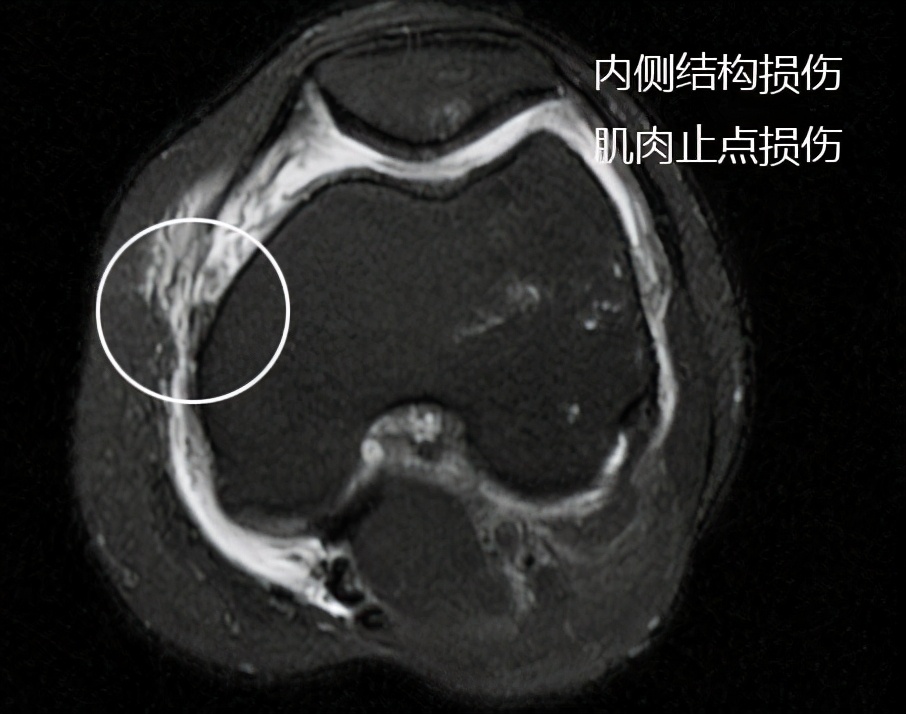

老爷子的核磁与预估得差不多,但是有它的特殊之处,在查体的时候,我们发现老爷子关节内侧方向的稳定性并不是特别的好,本以为是内侧副韧带发生了较大撕裂,但是在核磁上我们发现内侧副韧带损伤相对来讲不是特别的严重,而内侧肌肉撕裂相对来讲比较明显。